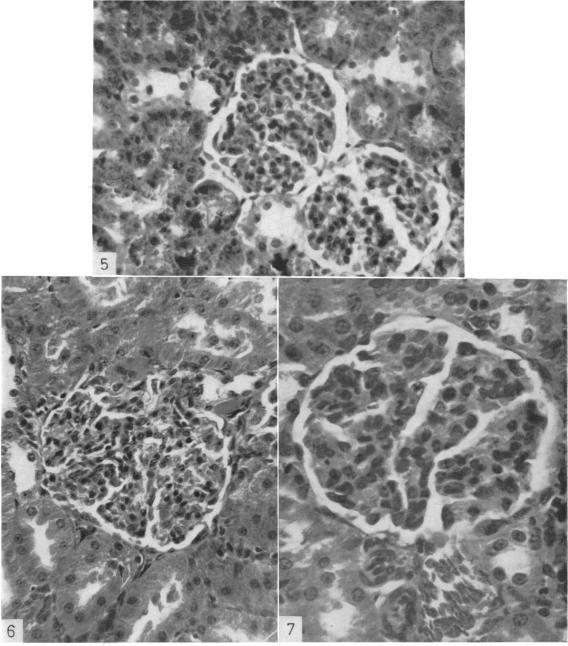

Rats were immunized by one to eight intraperitoneal administrations of species-homologous kidney fractions (prepared according to Ryan's differential centrifugation technique) emulsified in Freund's complete adjuvant. Proliferative and membranous glomerulitis ensued in about one-third of animals receiving five or more injections of any of the four renal preparations, i.e. heavy particle, mitochondrial, microsomal and soluble fractions. A significant increase in the incidence and titre of complement-fixing antibodies to renal antigens occurred, beginning with the third injection in rats sensitized with the heavy particle material and soluble fraction, and possibly also with the microsomal fraction; the mitochondrial fraction was ineffective in this respect. In this as in previous studies, neither a positive nor a negative correlation was established between the development of renal disease and the formation of circulating antibodies, glomerulitis frequently being found in the absence of detectable antibodies and vice versa. It is hypothesized that immunization with renal antigens elicits an immune response in the wake of which two independent processes are observed, namely the development of renal disease and the formation of circulating antibodies.

用弗氏完全佐剂乳化的同种肾部分(根据瑞安的差速离心技术制备)对大鼠进行1至8次腹腔注射免疫。在接受5次或更多次注射4种肾制剂(即重颗粒、线粒体、微粒体和可溶性部分)中任何一种的动物中,约三分之一出现了增殖性和膜性肾小球肾炎。在用重颗粒物质和可溶性部分致敏的大鼠中,从第三次注射开始,针对肾抗原的补体结合抗体的发生率和滴度显著增加,微粒体部分可能也是如此;线粒体部分在这方面无效。在本研究以及之前的研究中,肾病的发展与循环抗体的形成之间均未建立正相关或负相关,肾小球肾炎常常在未检测到抗体的情况下出现,反之亦然。据推测,用肾抗原免疫会引发免疫反应,在此之后会观察到两个独立的过程,即肾病的发展和循环抗体的形成。